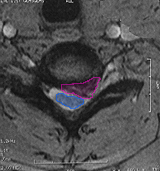

Κήλη αυχενικού μεσοσπονδυλίου δίσκου (φούξια πλαίσιο), με στένωση του νευρικού τρήματος και πίεση του εξερχόμενου νεύρου. |